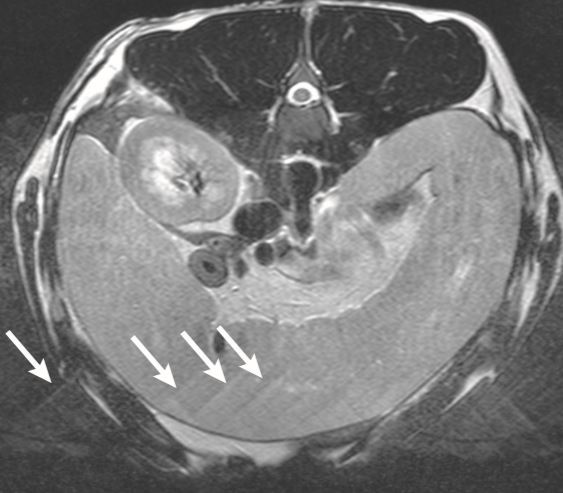

What is this artifact?

A

Flow related intravoxel dephasing

15

Q

Why does flow-related intravoxel dephasing occur?

Different velocities of flow are present in the same voxel. So they have picked up different amounts of phase and there for likely cancel each other out. Causing reduction of signal